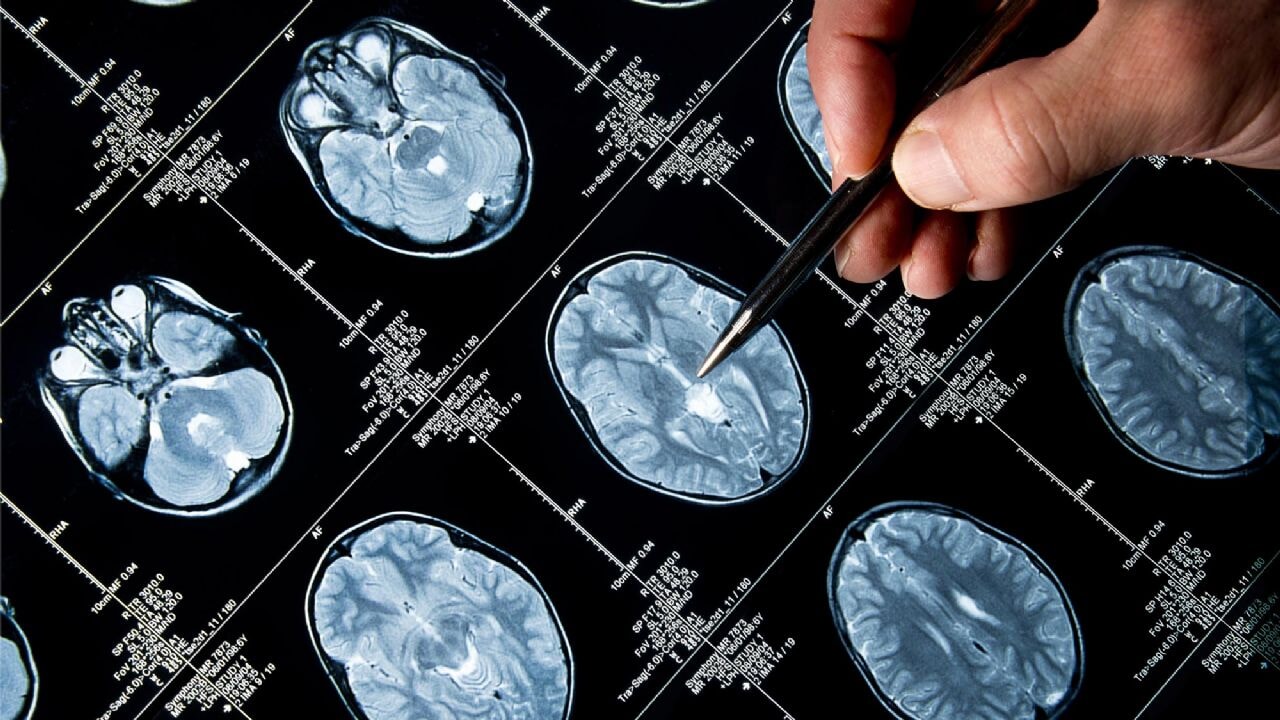

9, 32, 66 ve 83... Beyin ne zaman 'yetişkin moduna' geçiyor?

4 bin kişinin beyin taramalarında, insan beyni gelişiminin aralıksız değil, dört kritik 'dönüm noktası' ile ayrılmış beş ana dönemde gerçekleştiği ortaya koyuldu.

Fotoğraf: Arşiv

Cambridge Üniversitesi'nden sinir bilişimi araştırmacısı Prof. Duncan Astle liderliğindeki bu kapsamlı çalışma, bebeklikten yaşlılığa kadar sinirsel bağlantılarımızın nasıl değiştiğini haritalandırdı. Çalışma, beynin mimarisindeki büyük değişimlerin yaşandığı dört kritik dönüm noktası belirledi: 9, 32, 66 ve 83 yaşları.